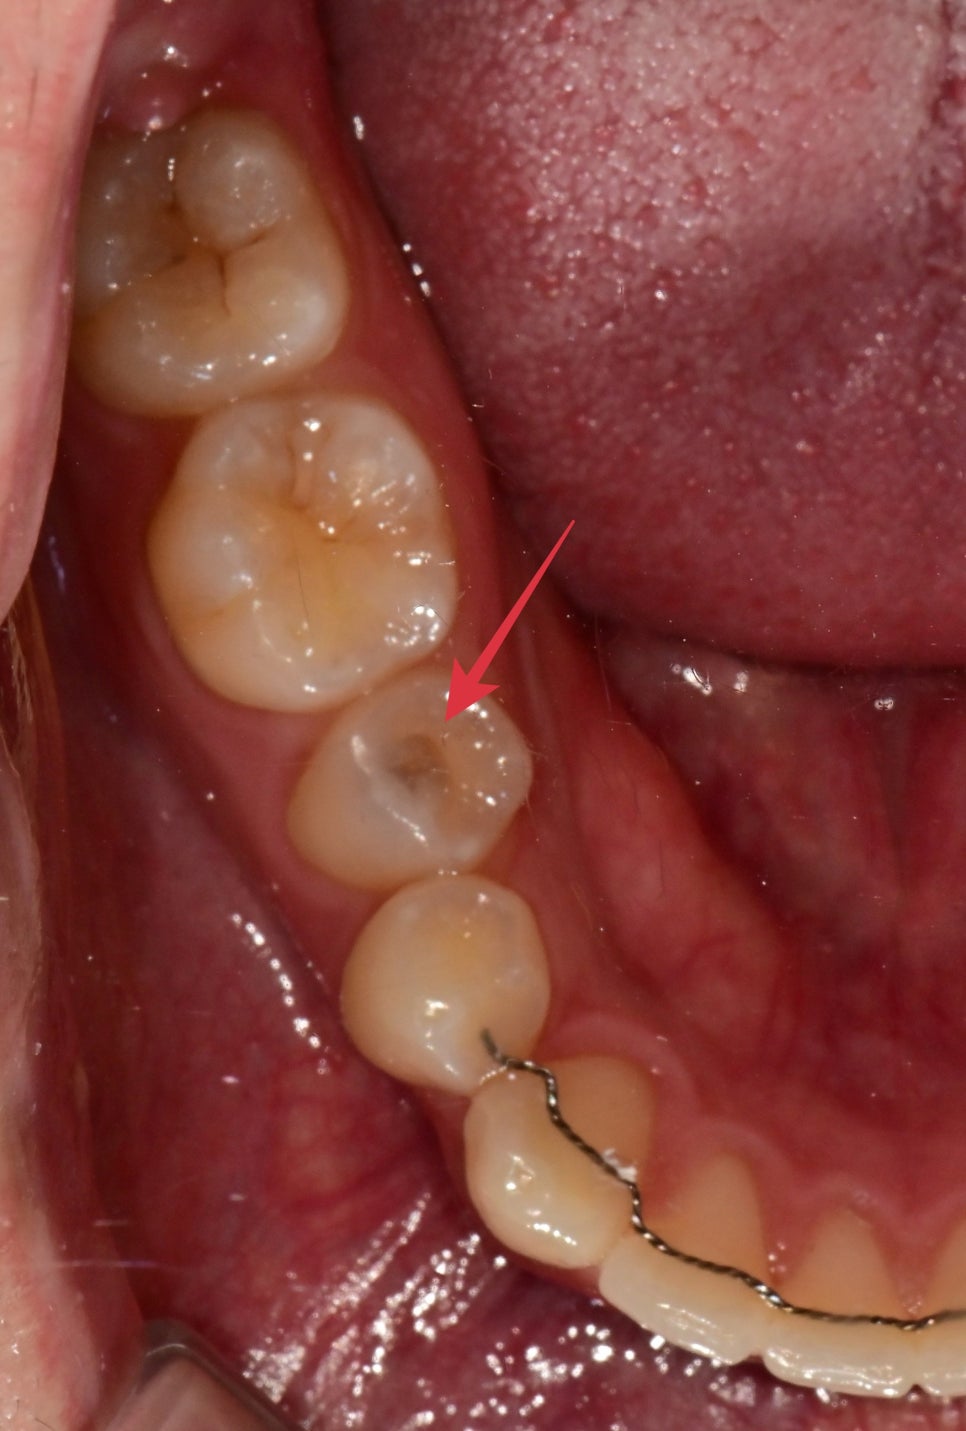

스케일링 겸 다른 부위 검진을 받기 위해 내원하셨습니다.

검진 결과 화살표에 표시된 작은 어금니 씹는면쪽에

안쪽으로 어둡게 비춰 보이는 충치가 진행 중이었습니다.

항상 충치가 있다고 통증이 무조건 수반되는 것은 아닙니다.

천천히 진행되거나 우리가 알아차릴 수 없는 정도의 통증으로 인해

충치를 자가 발견을 하는 것은 쉬운 것이 아닙니다.